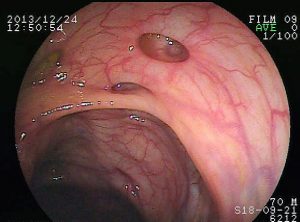

I diverticoli sono piccole sacche che si formano nel rivestimento del colon e dell’intestino e che presentano un rigonfiamento verso l’esterno. Sono in pratica delle alterazioni anatomiche molto diffuse e particolarmente legate all’età: circa il 65% della popolazione adulta ha la diverticolosi ossia la presenza di queste sacche nelle pareti dell’intestino. Come vedremo, questa condizione è più frequente nelle donne e tende a peggiorare con l’avanzare dell’età. La diverticolosi, di per sè, non è una patologia ma solamente un’alterazione anatomica e non deve essere confusa con la diverticolite che, al contrario, è l’infiammazione dei diverticoli.

DiverticoliCome abbiamo accennato, i diverticoli sono delle estroflessioni che si formano lungo le pareti dell’intestino: dei rigonfiamenti che di per sé non provocano alcun tipo di disturbo. La diverticolosi è una condizione che può essere in alcuni casi congenita ma che è spesso determinata da una dieta sbilanciata e povera di fibre. I diverticoli infatti, secondo la teoria medica più accettata, si formano come conseguenza di una povera mobilità intestinale, causata a sua volta da un’alimentazione scorretta. Per questo motivo la diverticolosi è ormai diventata una condizione sempre più diffusa, specialmente negli USA e nei Paesi occidentali. Chiamata spesso anche “malattia del benessere”, può essere associata ad una dieta troppo ricca di grassi e di zuccheri e povera di fibre.

E’ importante distinguere la diverticolosi dalla diverticolite, perchè mentre la prima è una pura e semplice alterazione anatomica la seconda è una vera e propria patologia. Mentre infatti la diverticolosi è la presenza di diverticoli e non comporta quasi mai una sintomatologia associata, la diverticolite è l’infiammazione di queste estroflessioni ed è quindi a tutti gli effetti una patologia che deve essere trattata.